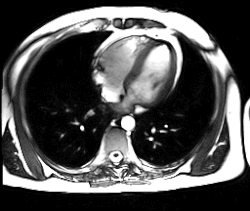

Battements cardiaques filmés en IRM ; seuls les ventricules sont visibles.

• L'IRM cardiaque est l'examen radiologique de référence pour l'exploration du muscle cardiaque lui-même, principalement pour les tumeurs cardiaques.